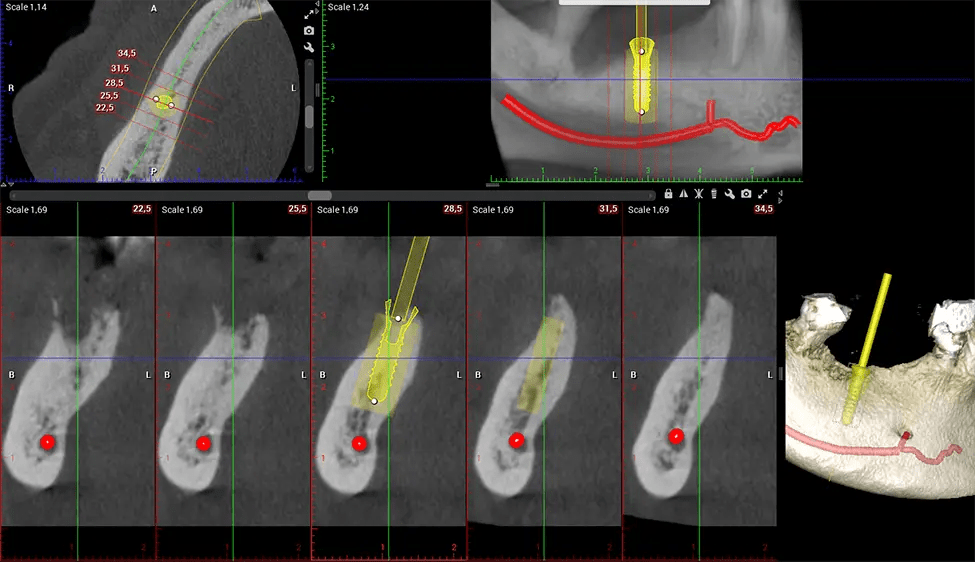

This 3D scan, called cone beam computed tomography, gives your dentist a more complete image of your oral anatomy and disease processes than a traditional X-ray. Unlike conventional X-rays, which capture a 2D image of your mouth from various angles, a 3D scan takes multiple digital X-rays for one image. It provides a complete view of your jaw, teeth, nerves, and soft tissues. This enhanced view allows dentists to detect minor issues not visible in traditional 2D scans, such as impacted wisdom teeth or bone fractures in the sinus cavity.

Another significant benefit is that 3D imaging provides more precise images of your bone structure. These images are more detailed, providing you with a more accurate diagnosis. An accurate diagnosis means better treatment for you.

When paired with extractions, dental implant placement, or bone grafting, CBCT technology can provide you with a quicker and much more comfortable experience. This is because the 3D image provides a more detailed picture of your entire oral cavity, allowing your dentist to walk you through each step of the process before it occurs. This often helps patients feel more prepared and comfortable overall, especially if they have had a traumatic experience with past dental treatments.

After the scanning process, the captured X-ray images are processed by the CBCT software, which applies algorithms to reconstruct a detailed 3D image of the scanned area. The software compiles these individual X-ray images and creates a digital 3D representation of the patient’s anatomy. The reconstructed 3D CBCT image can be viewed and analyzed by the dentist or radiologist. This image can be manipulated, rotated, and zoomed in or out to examine specific structures and evaluate the patient’s condition.

Our patented SCARA technology enables doctors to capture True Extraoral Bitewings that are as accurate at detecting caries as a 2D bitewing series, but with half the radiation dose. With our bitewings, doctors can view the apices of teeth on both jaws providing a more comprehensive view of the patients’ anatomy.